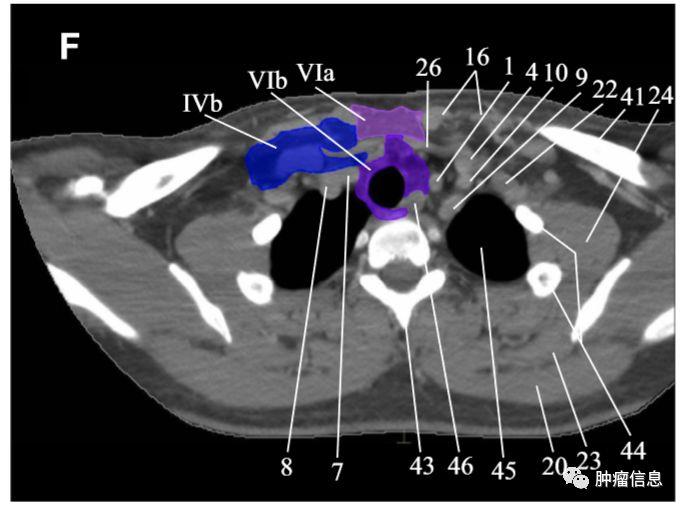

RTOG2013年头颈部淋巴结分区勾画图谱:

Ia:颏下淋巴组Ib:颌下淋巴组II:上颈淋巴组III :中颈淋巴组IVa:下颈淋巴组IVb:锁骨上内侧组V:颈后三角淋巴组Va:上颈后三角淋巴组Vb:下颈后三角淋巴组Vc:锁骨上外侧组VI:颈前淋巴组VIa:颈前淋巴结VIb:喉前、气管前、气管旁淋巴结VII:椎前淋巴组VIIa:咽后淋巴结VIIb:茎突后淋巴结VIII:腮腺淋巴组IX:面颊淋巴组X:颅底后组Xa:耳后、耳下淋巴结Xb:枕淋巴结见下图:

颈部VII区淋巴结

上纵隔淋巴结上界:胸骨上窝下界:主动脉弓上缘两侧界:颈总动脉

颈部VII区Ⅶ区淋巴结位于上纵隔(上纵膈淋巴结)。

胸部淋巴结分区范围及勾画

第1组淋巴结

下颈、锁骨上、胸骨切迹淋巴结上界:环状软骨下缘下界:锁骨、胸骨柄上缘气管中线为1L和1R的分界线。